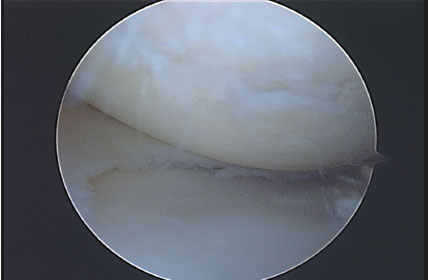

Todos los pacientes que realizaron su RM de rodilla en el Servicio de Diagnóstico por Imágenes del Hospital Británico, y luego fueron operados de su rodilla en el mismo Centro durante el mes de Abril de 2009, fueron incluidos en el presente trabajo. Es un estudio con un diseño transversal, con recolección de datos retrospectiva, nivel de evidencia III. Un total de 43 pacientes fueron incluidos. Dos pacientes fueron excluidos del análisis por alteración de la imagen de resonancia, uno por artefacto del movimiento durante el estudio y el otro por artefacto producido por material de osteosíntesis colocado en la rodilla en una intervención previa. De los 41 pacientes evaluados en el estudio, el promedio de edad fue de 50 años (21-71). Fueron 27 hombres y 14 mujeres evaluados. El intervalo de tiempo promedio entre la realización de la RM y la cirugía fue de 63 días (6-275 d). Veintinueve pacientes (70,73 %) fueron intervenidos dentro de los 2 meses de realizada la RM. Se realizó una revisión de las historias clínicas para corroborar que ningún paciente refirió alguna lesión durante ese intervalo de tiempo. En todos los casos se realizó una RM con un equipo Philips de 1,5 Tesla, realizando en todas ellas cortes de reconstrucción axial, coronal y sagital, para evaluar adecuadamente la articulación en toda su extensión. Cada estudio de RM fue analizado en forma retrospectiva por dos observadores ciegos de los resultados obtenidos luego en la cirugía, ambos trabajaron en forma conjunta. Uno de los evaluadores (M.C) es médico de planta del Servicio de Diagnóstico por Imágenes del Hospital (especialista en RM músculo esquelética); el otro evaluador (L.C) es Jefe de Residentes de Diagnóstico por Imágenes del Hospital. Ambos estudiaron cada caso en particular, y debían valorar el cartílago en cada zona articular y establecer un único resultado. Seis superficies articulares fueron evaluadas: rótula, tróclea, cóndilo femoral medial y lateral, platillo tibial medial y lateral. El cartílago articular fue clasificado en la RM y en la artroscopia de acuerdo a la clasificación de Johansson. (7) El Grado 0 indica cartílago intacto; grado 1 ablandamiento o edema de cartílago; grado 2 fibrilación de cartílago; grado 3 ulceración superficial o fisura que comprometen menos del 50% del espesor del cartílago; grado 4 ulceración profunda o fisuras que comprometen ás del 50% del espesor de cartílago; grado 5 lesión de espesor completo con hueso expuesto; grado 6 lesión en espejo, con hueso expuesto en ambas superficie enfrentadas. Todas las lesiones condrales debieron ser confirmadas en al menos 2 cortes de RM. Se confeccionó en cada caso un registro escrito de cada paciente con los grados de lesión condral en cada superficie. (Ver Figs. 1 a 4)

Figura 3: Lesión condral de espesor menor al 50 %. Corresponde a un grado 3.